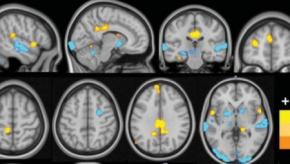

Read ArticleA Neural Signature in Fibromyalgia

Fibromyalgia is a well characterized condition with disordered pain processing. Although the clinical constellation and diagnostic clues are well characterized, FM lacks a diagnostic biomarker and most imaging and tissue diagnostics have been unrevealing.